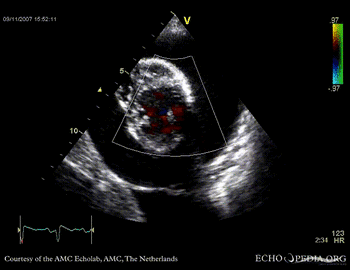

Case 14

Tamponade

Courtesy of:

J. Vleugels, AMC, The Netherlands

tamponade 11